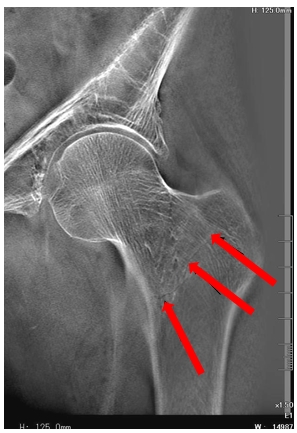

病例三:男,85歲。左髖摔傷6小時(shí)。

患者具有嚴(yán)重的骨質(zhì)疏松,斷層融合能夠清晰的顯示骨小梁不連續(xù)的情況,對診斷有很大的幫助。